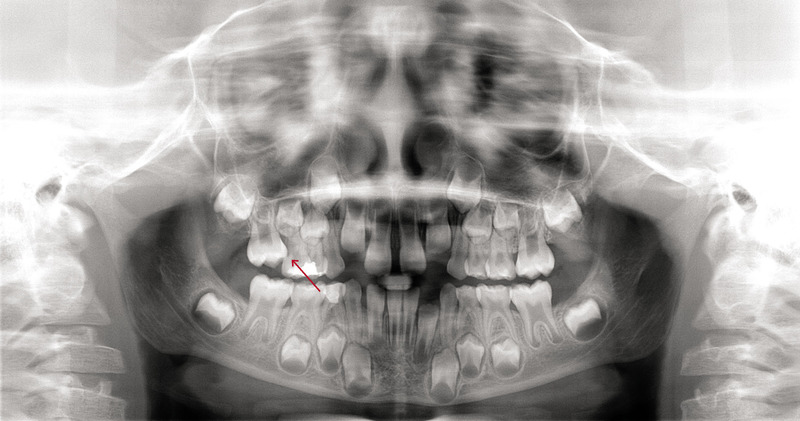

Rozpoznanie wyrzynania ektopowego opiera się na badaniu klinicznym oraz diagnostyce radiologicznej. Stomatolog lub ortodonta ocenia położenie zęba oraz jego wpływ na pozostałe struktury jamy ustnej.

Zdjęcia RTG pozwalają dokładnie określić kierunek wyrzynania oraz zaplanować odpowiednie leczenie.